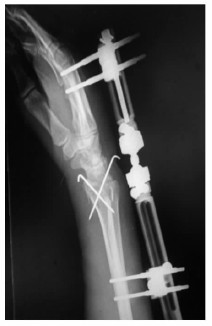

1.2 治疗方法急诊予以常规患侧腕关节正侧位X线片,必要时CT三维重建(图 1、2)。均采用臂丛麻醉,仰卧位,常规消毒铺巾,止血带止血。开放者直视下克氏针穿针固定,闭合骨折由助手牵引,手法复位纠正侧方移位,成角及短缩畸形,术中X线透视,骨折块或关节面复位不满意可借助克氏针撬拨复位或有限切开复位,复位满意后用多枚克氏针交叉固定。克氏针以刚穿出骨皮质为宜,以增加牢度,克氏针尾部折弯留于皮外,骨折初步复位后予以安装动力型外固定架,选择超关节外固定架,先于第二掌骨背外侧作2个0.5 cm切口,间距以外固定架钉夹为准,平行植入2枚2.5 mm支架螺钉,在距桡骨骨折线4~6 cm桡骨上置入2枚支架螺钉,安装并调整外固定架,保证远端球形活动关节位于桡腕关节水平线上,利于早期功能锻炼,同时调整外固定架施以适当牵引力,保持腕关节轻度尺偏掌曲位并锁紧,直至透视满意。术后第2天开始手指伸屈曲能锻炼,术后第1天,4周,6周、8周及3个月复查X线片(图 3、4),4周松外固定架锁紧装置开始功能锻炼,4~6周拔除克氏针,6~8周拆除外固定架。

| 图 4 术后4周侧位片 |